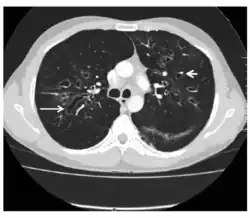

CT showing ‘signet ring’ (short, thick arrow) and ‘string of pearls’ (long, thin arrow) appearances, indicative of central bronchiectasis. Mucoid impaction and dilated bronchi are also seen.